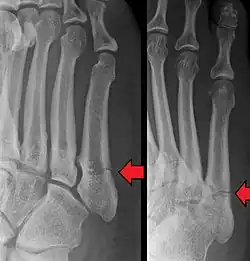

Diagnostic X-rays include anteroposterior, oblique, and lateral views and should be made with the foot in full flexion.

- Proximal diaphysis, typically stress fracture.[12][13]

- Metaphysis: Jones fracture[14]

-Tuberosity: Pseudo-Jones fracture[15] (avulsion fracture).[15]

Normal anatomy:

- Apophysis: Normal at 10 - 16 years.[16]

- Os vesalianum, an accessory bone.[17]

Other proximal fifth metatarsal fractures exist, although they are not as problematic as a Jones fracture. If the fracture enters the intermetatarsal joint, it is a Jones fracture. If, however, it enters the tarsometatarsal joint, then it is likely an avulsion fracture caused by pull from the fibularis brevis tendon. An avulsion fracture at the base of the fifth metatarsal is sometimes called a "dancer's fracture" or a "pseudo Jones fracture", and usually responds readily to non-operative treatment.[18] The X-ray appearance of the developmental "apophysis" in this area may have some resemblance of a fracture, but is not a fracture; it is the secondary ossification center of the metatarsal bone. It is a normal finding that occurs at this site in adolescents.[19] If an injury to that area has occurred, the physician is often able to interpret certain radiographic clues to make the differentiation. An avulsion fracture at this location is typically extra-articular and oriented transversally as compared to the longitudinal orientation of an unfused apophysis.[19]